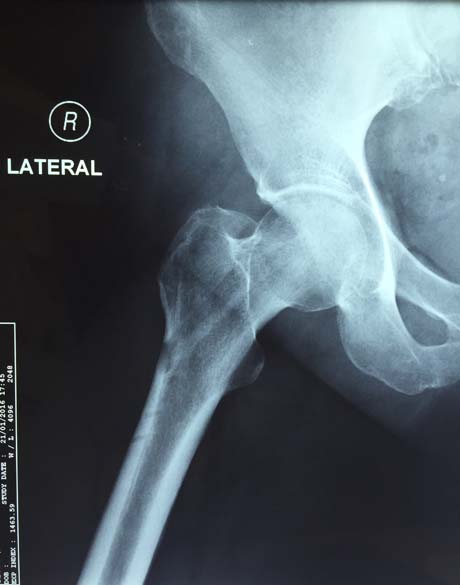

Female 51 years old with pain in the right hip from 3 months ago. Examination MRI showed osteonecrosis of the femoral head right.

Under fluoroscopic control carried out targeting the defect – aseptic necrosis of femoral head right

Opening bone tunnel to the point of osteonecrosis of the femoral head

Post-op X-ray of the right hip

Hip X-ray 5 months post-op